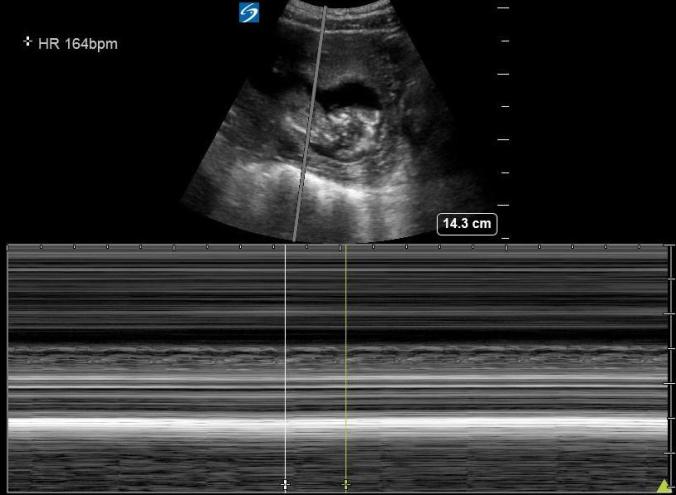

D. M-Mode FHR (optional)